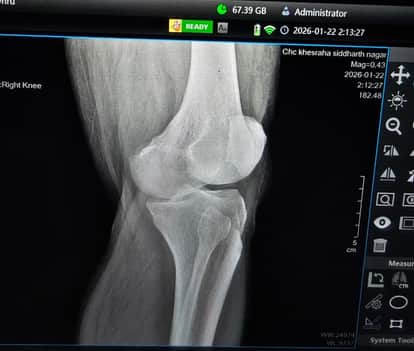

उसका बाजार(सिद्धार्थनगर)। जिले के सामुदायिक स्वास्थ्य केंद्र खेसरहा पर कई महीनों से एक्स-रे प्लेट नहीं है। इससे मरीजों की परेशानी बढ़ गई है। इसकी पोल तब खुली जब सोमवार को शिक्षक विधायक ध्रुव कुमार त्रिपाठी घुटने में दर्द की समस्या पर एक्स-रे करवाने खुद अस्पताल पहुंचे। एक्स-रे की फिल्म ने मिलने पर नाराज हो गए और मामले को सदन में उठाने की बात कही।

दरअसल, शिक्षक विधायक ध्रुव कुमार त्रिपाठी क्षेत्र के भावपुर गांव में दंपति की मौत परिवार से मिलकर सांत्वना देने के लिए गए थे। इसी बीच घुटने में दर्द महसूस हुआ तो क्षेत्र के सामुदायिक स्वास्थ्य केंद्र खेसरहा पहुंचे। जहां समस्या बताने पर एक्स-रे हुआ। जब रिपोर्ट और फिल्म की बात आई तो फोटो लेकर विधायक के मोबाइल पर भेजने की बात कही। इस पर एमएलसी ध्रुव कुमार त्रिपाठी ने कहा कि उन्हें प्लेट डॉक्टर को दिखानी है, जिससे इनका इलाज हो सके। टेक्निशियन ने इसके लिए असमर्थता जताई और बताया कि कई दिनों से यहां एक्स-रे प्लेट नहीं है। अस्पताल में यह अव्यवस्था देखकर शिक्षक विधायक ने रोष प्रकट किया और इस समस्या की शिकायत उच्चाधिकारियों से करने के साथ सदन में भी उठाने की बात कही है।